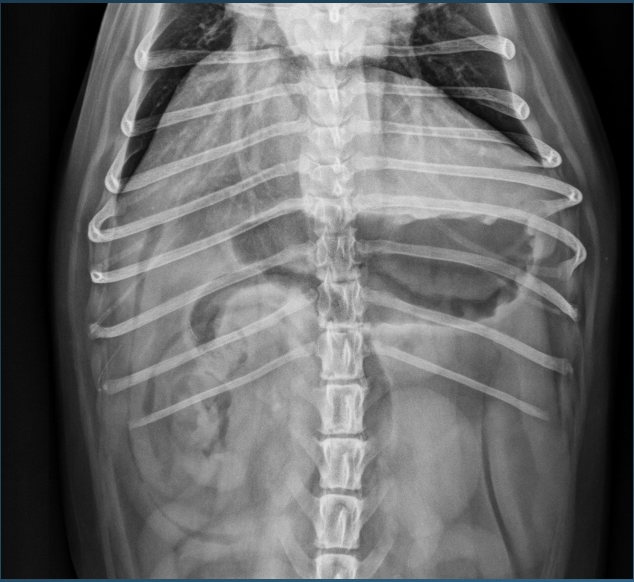

What is shown in this image?

A

normal right lateral view in the dog